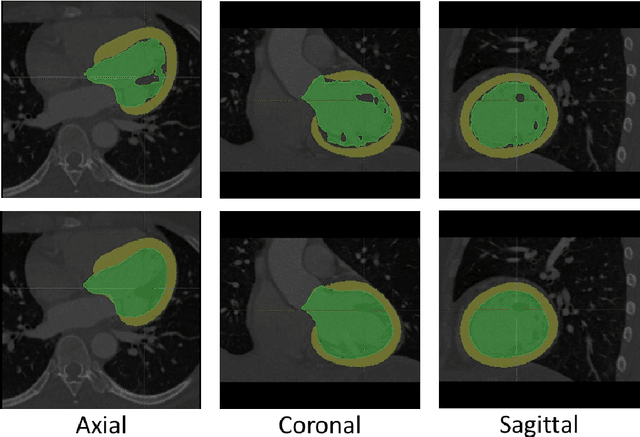

Abstract:The training of deep learning models typically requires extensive data, which are not readily available as large well-curated medical-image datasets for development of artificial intelligence (AI) models applied in Radiology. Recognizing the potential for transfer learning (TL) to allow a fully trained model from one institution to be fine-tuned by another institution using a much small local dataset, this report describes the challenges, methodology, and benefits of TL within the context of developing an AI model for a basic use-case, segmentation of Left Ventricular Myocardium (LVM) on images from 4-dimensional coronary computed tomography angiography. Ultimately, our results from comparisons of LVM segmentation predicted by a model locally trained using random initialization, versus one training-enhanced by TL, showed that a use-case model initiated by TL can be developed with sparse labels with acceptable performance. This process reduces the time required to build a new model in the clinical environment at a different institution.